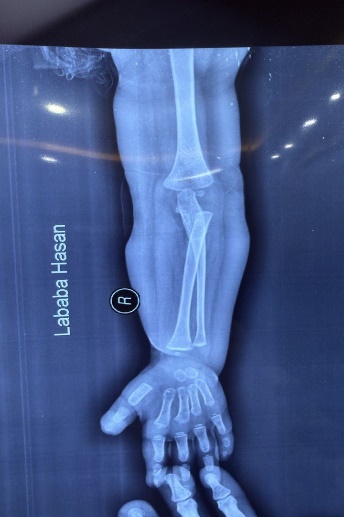

Figure 2: Hands and feet deformities

Short, broad hands and feet with clenched fingers and bilateral clubfoot, consistent with skeletal anomalies described in HPMR

Skeletal: Short broad hands/feet, clenched fists, bilateral clubfoot.

Figure 11: Skeletal deformities of the upper and lower limbs

Photographs showing short, broad hands with clenched fingers (upper image) and bilateral clubfoot deformities (lower image), consistent with skeletal abnormalities described in HPMRS.